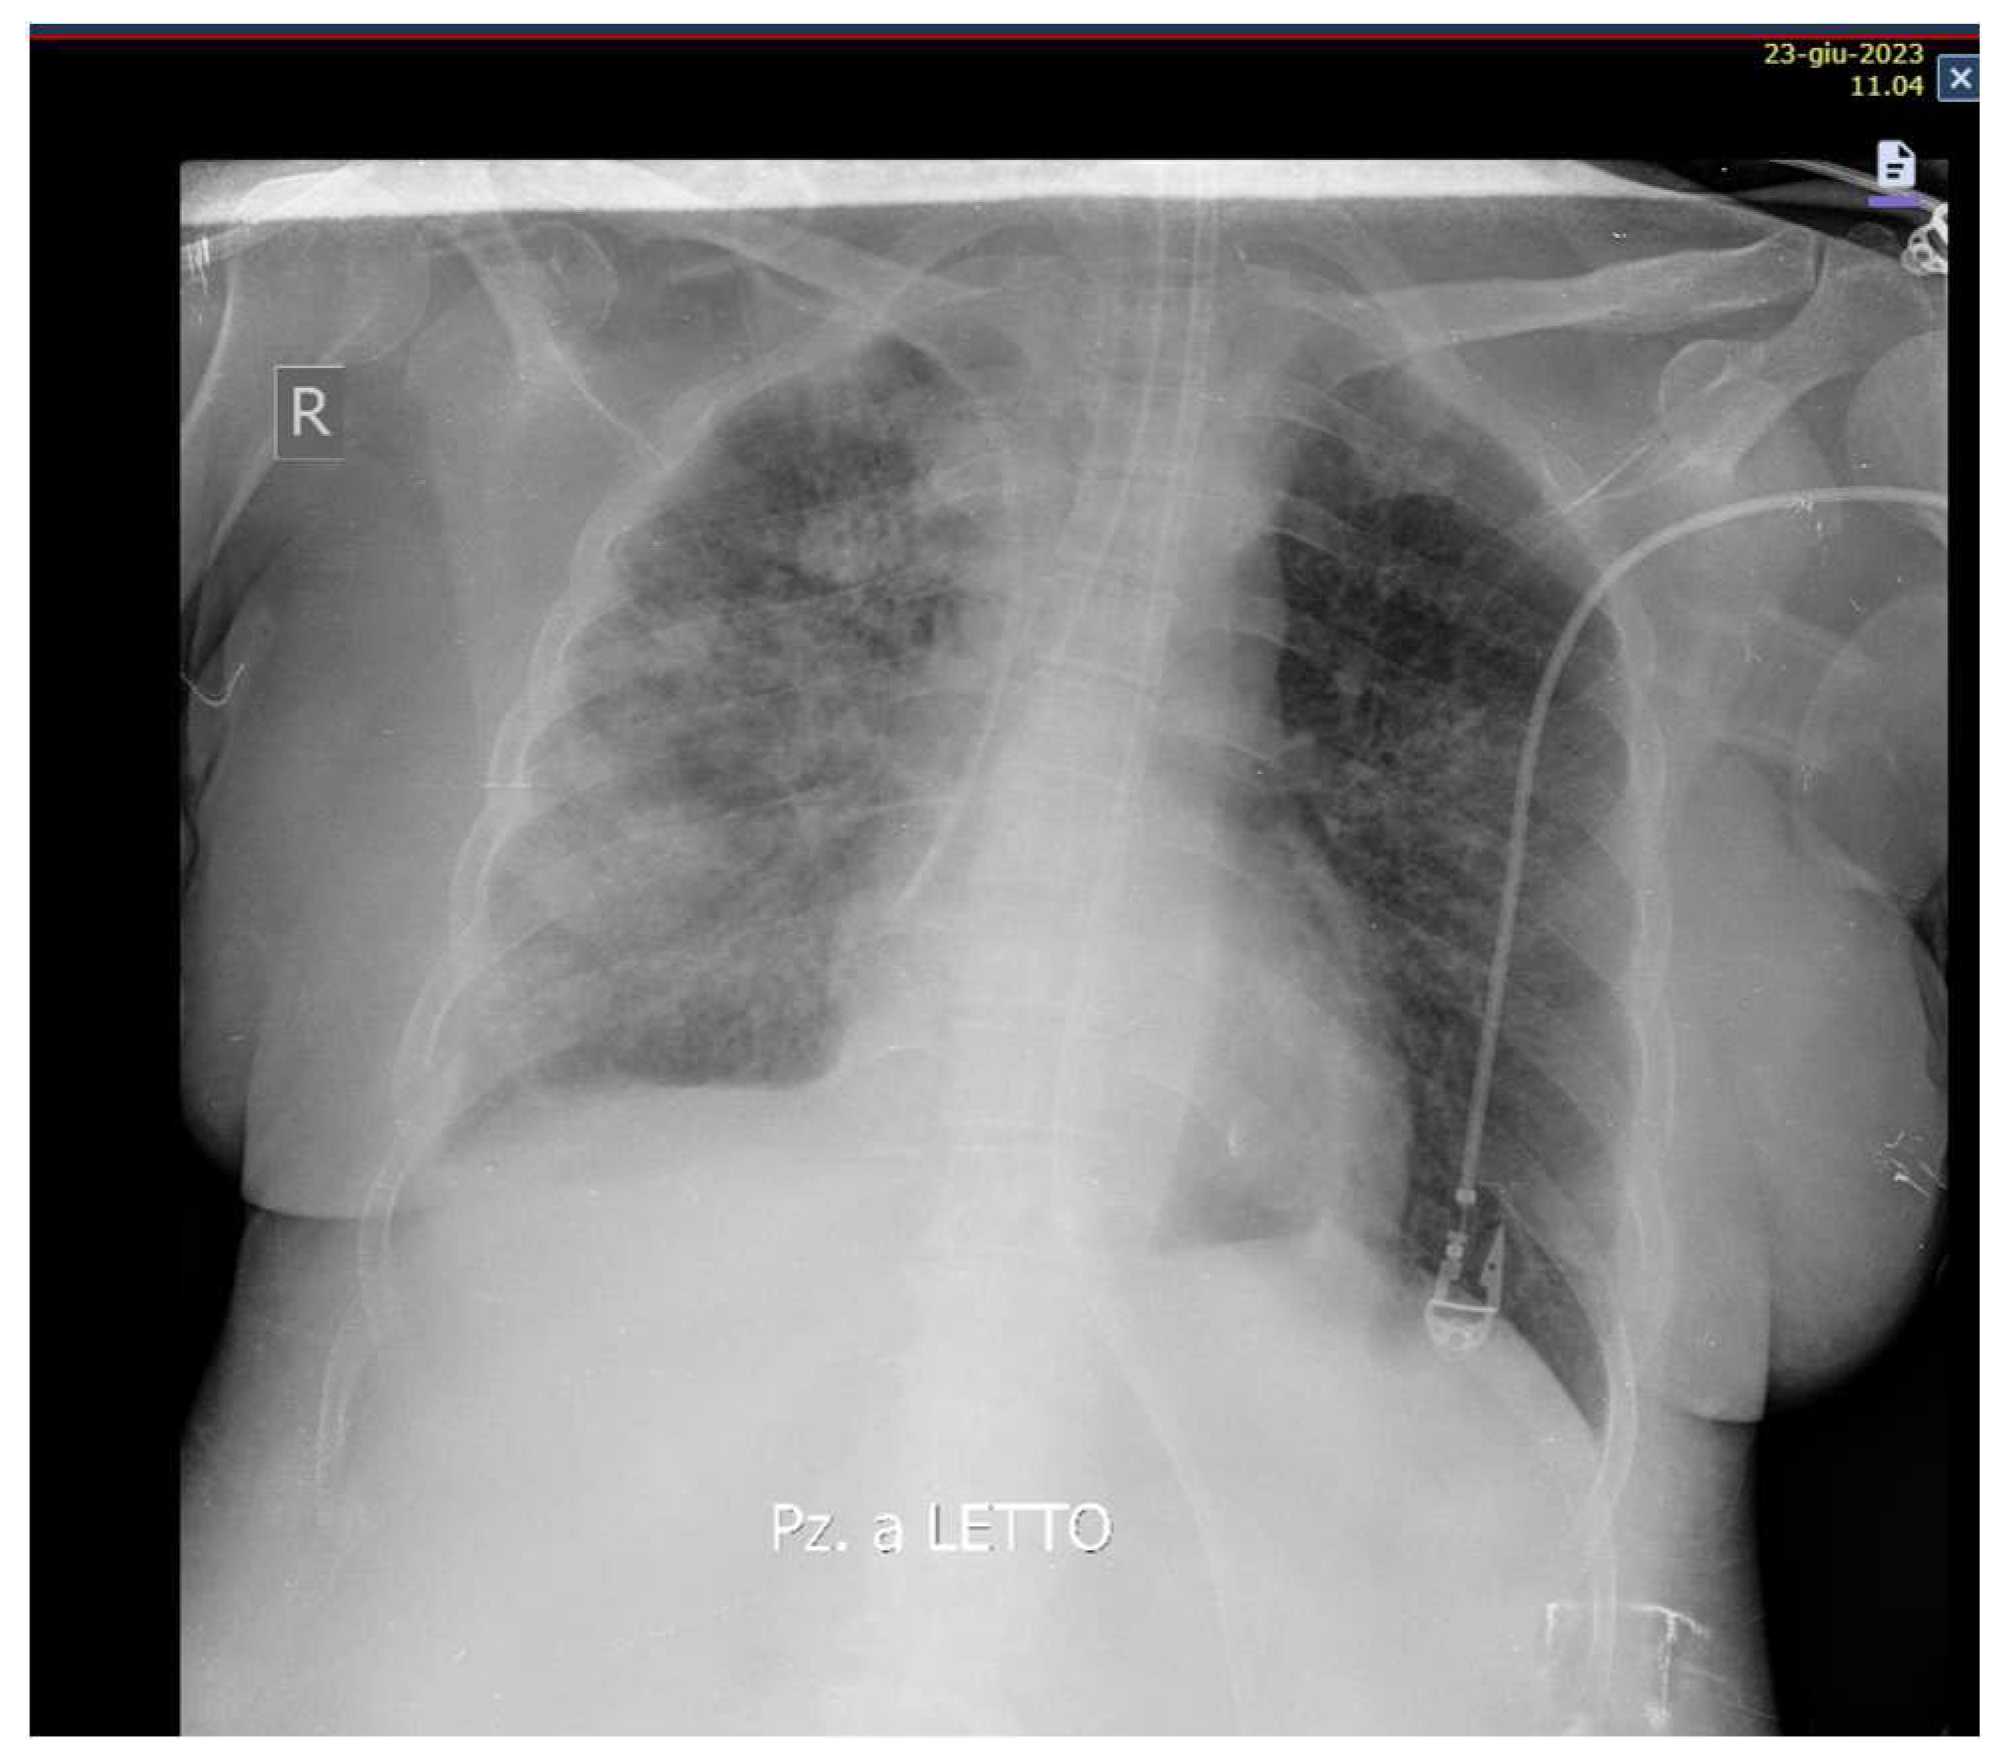

Likewise, an improvement in respiratory exchanges and radiological images was observed (Figure 3).

Figure 3. Chest x-ray 48 hours after starting Ganciclovir therapy.